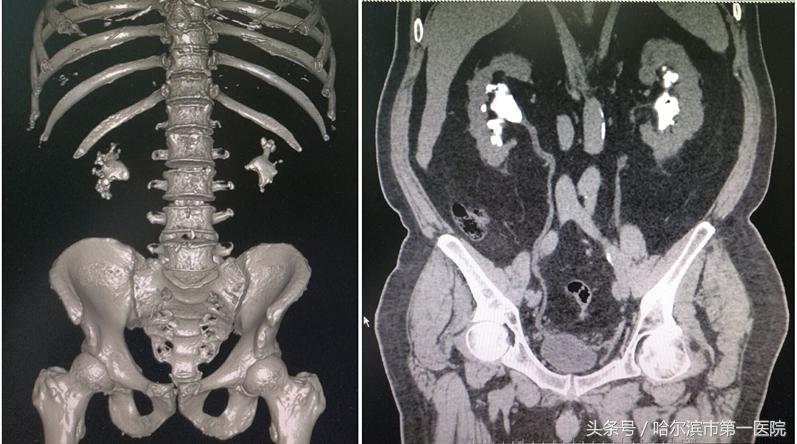

铸型结石术前三维CT影像

检查中发现,曹先生的结石最大径线45×36mm,像一个“鹿角”一样,已经塞满了左侧肾盂和各个肾盏。经过术前讨论后,具有多年微创碎石取石经验的哈尔滨市第一医院泌尿外科专家孙长华主任采取了“经皮肾镜超声碎石取石”的治疗方案。术中通过用超声在左侧后腰精准定位,然后打一个直径约0.8公分的通道,用超声弹道碎石系统击碎结石,并将碎石吸出体外,仅用半个小时,就彻底清除巨大结石。术后复查,无结石残留,6天后病人痊愈出院。